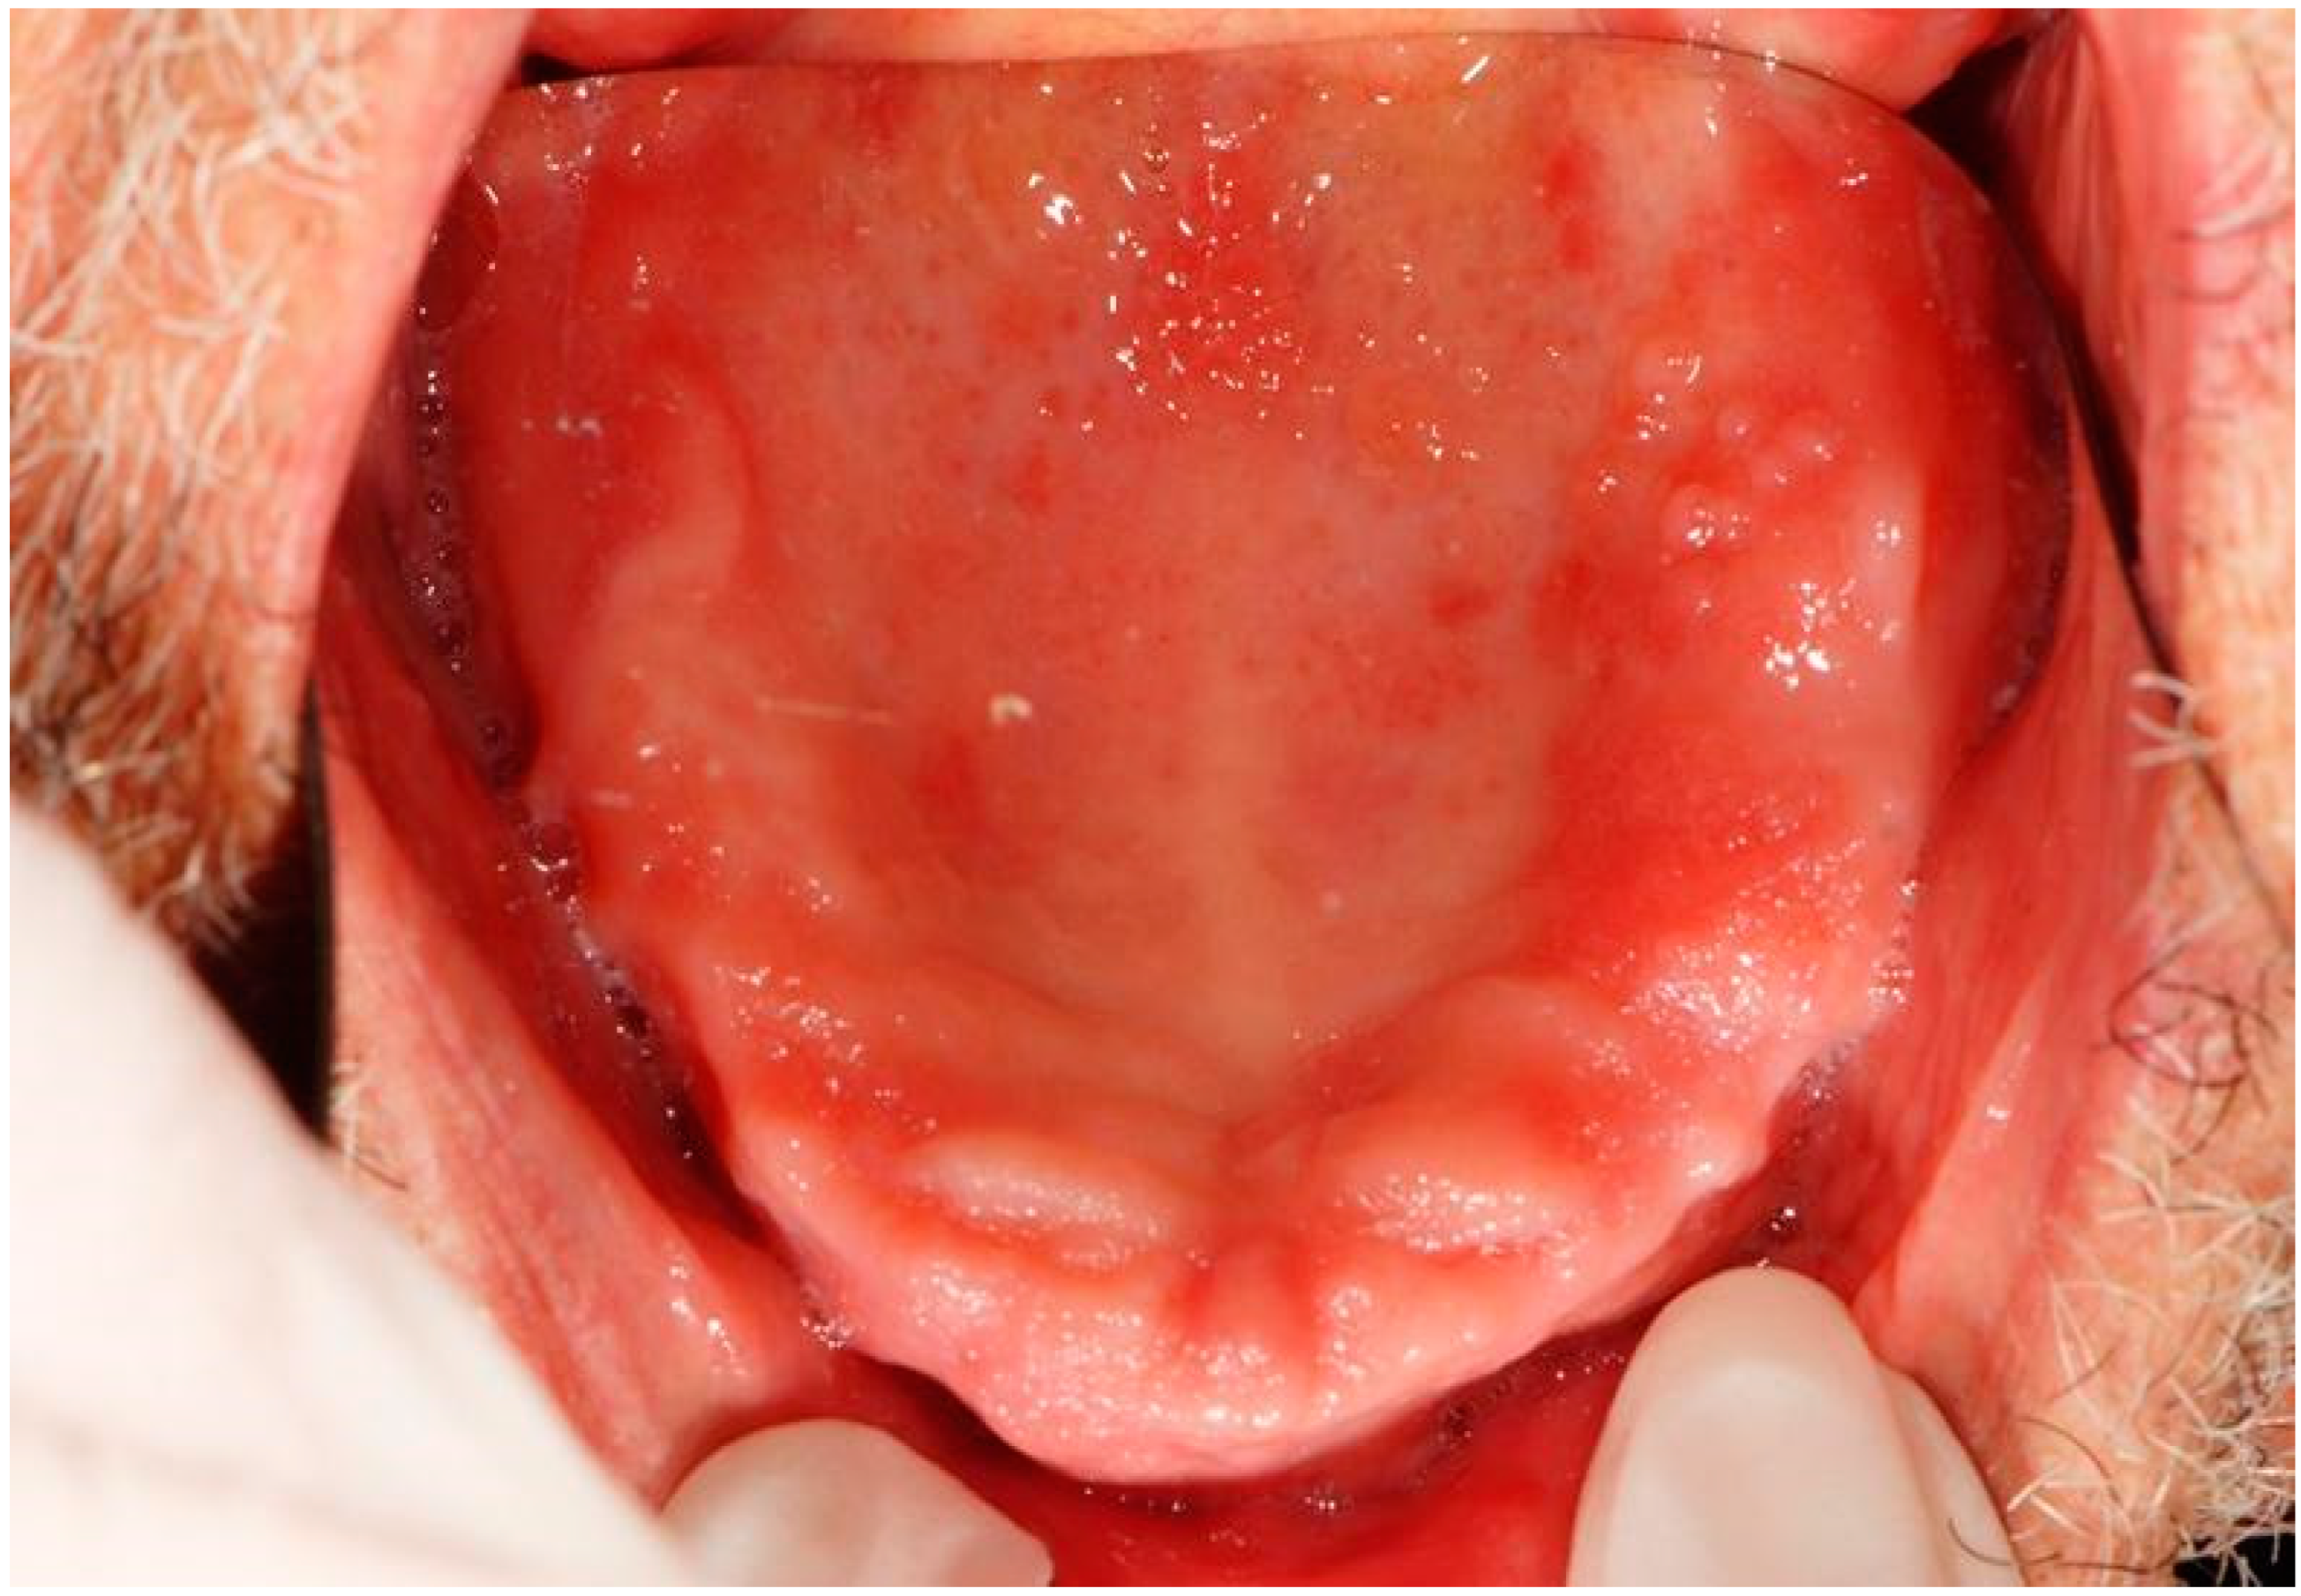

| 4 | Removable whitish plates Erythematous area Xerostomia | Candidiasis (pseudomembranous candidiasis, median rhomboid glossitis) | Dorsal tongue Oral mucous membranes | Nystatin Mucosamin® mouthwash | 3rd dose 9th dose |

| 10 | Erythematous and ulcerative areas | Epithelial atrophy without dysplasia Ulcer | Palate | 2nd dose | |

| 12 | Non-removable whitish lesions | Epithelial atrophy and hyperkeratosis without dysplasia | Cheek Dorsal tongue | Aminogam® mouthwash | 4th dose |

| 13 | Erythematous area Ulcer Removable whitish plates | Epithelial atrophy without dysplasia Ulcer Candidiasis | Palate Tuberosity Dorsal tongue Alveolar process | Nystatin | 2nd dose 4th dose |